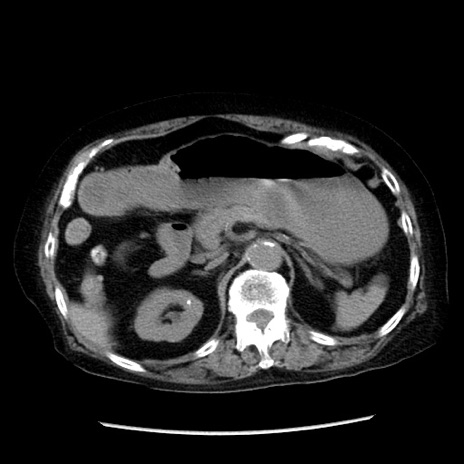

症例14(横断像)

【症例】 90歳代女性

【主訴】 腹痛・嘔吐

【現病歴】今朝から左側腹部痛を認めた。 経過観察していたが、嘔吐を認めたため来院。

【既往歴】 子宮癌術後

【身体所見】 意識清明、BP 127/54mmHg、P 98bpm Sp02 95%(RA)、BT 35.8°C、腹部平坦・軟腸ぜん動音聴取良好、右下腹部圧痛(+) 反跳痛なし

【データ】WBC 9800、CRP 0.46